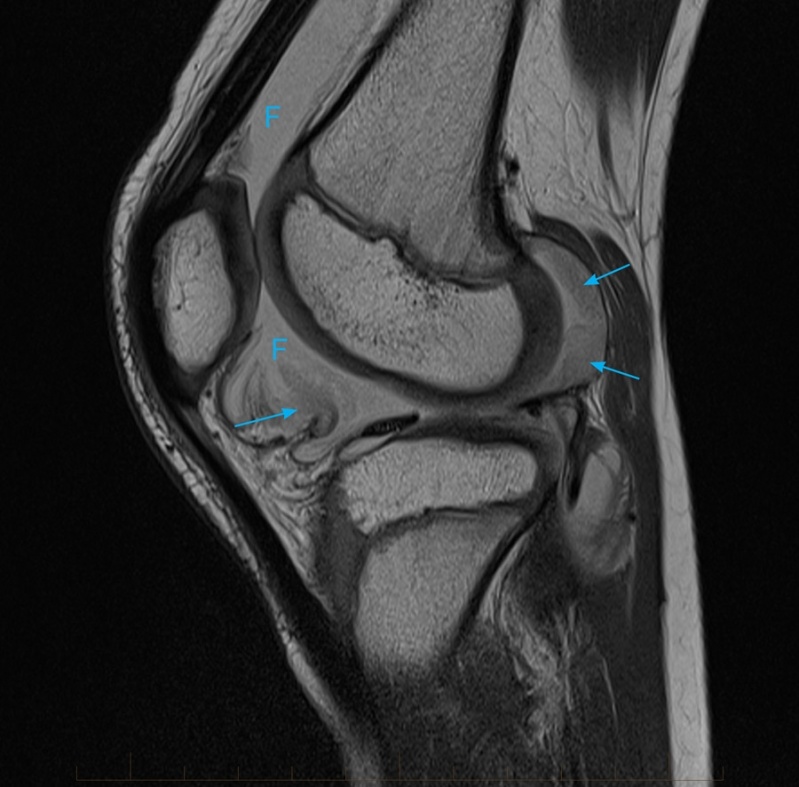

Exame de Imagem de Ressonância Magnética de Joelho

Exame de Imagem de Ressonância Magnética de Joelho

Exame de Imagem de Ressonância Magnética de Joelho

Medicom ExamesCom um exame de imagem é possível o médico analisar e ver o interior do corpo do paciente, para que desse modo seja possível dar um diagnóstico... Cotar Agora Saiba Mais